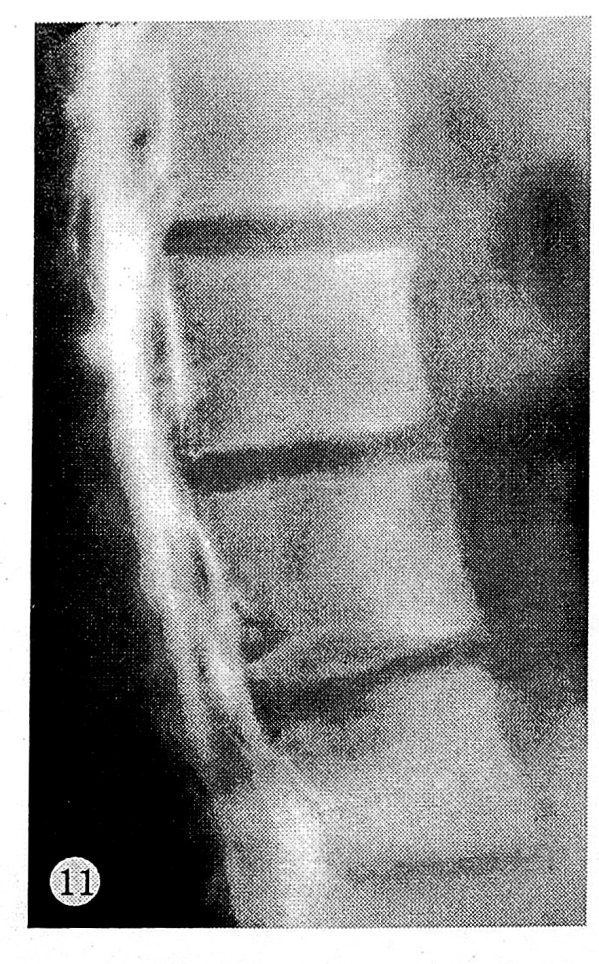

В 17 случаях контрастное вещество не выходило за пределы склеротической каймы вокруг грыж Шморля. Остальные 5 случаев демонстрировали дальнейшее продвижение контрастного вещества в глубь тела позвонка на 2—5 мм. Мы располагаем также двумя наблюдениями внутриспонгиозного пролабирования студенистого ядра без признаков грыжи Шморля на стандартных спондилограммах (см. рис. 5 и 11). Емкость диска составляла 1,0—1,8 мл. Введение контрастного вещества не сопровождалось болью. Высота межтеловых промежутков была умеренно снижена.

Рис. 11. Тело L4 позвонка без рентгенологических признаков грыжи Шморля.